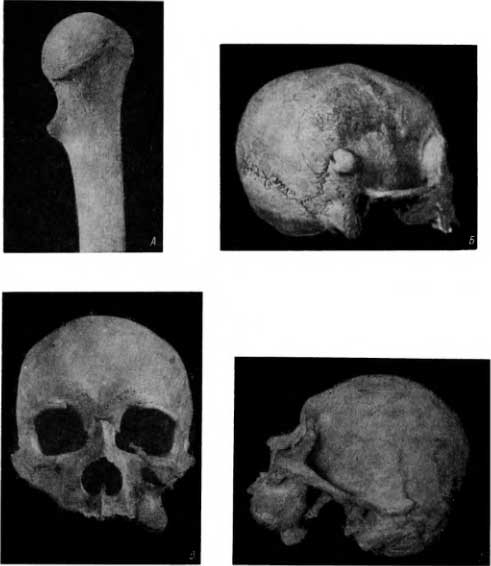

Рис. 61. Остеома. А — на проксимальном метафизе плечевой кости; Б — на чешуе височной кости; В — левой гайморовой полости шамана; Г — тот же череп в боковой проекции.

Среди костных материалов из погребений в Саркеле были еще 2 таких наблюдения. Второй случай остеомы (рис. 61, Б) был нами обнаружен на чешуе височной кости. Она, как и предыдущая остеома, не отличалась ни цветом, ни структурой от нормальных костей. Еще одна остеома располагалась на одной из плюсневых костей старика.

Очень редкая локализация остеомы наблюдалась у шамана XIX в. из Восточного Алтая. Это была остеома гайморовой полости (рис. 61, В и Г). Его лицо и без устрашающих одежд, пляски, бубна, пения и завывания в соответствии с убеждениями малокультурных людей могло должным образом действовать на злых демонов, пугать их.

В погребении в Эски-Кермене (VI–XII вв.) было обнаружено несколько костей с доброкачественными опухолями, среди них 2 остеомы: одна остеома локализовалась на затылочной кости (рис. 62, А), другая располагалась по нижнему краю почти у угла челюсти (рис. 62, Б). Как видно на снимке в другой проекции, это остеома на ножке (рис. 62, В).

Рис. 62. Остеома. А — затылочной кости; Б — на нижнем крае нижней челюсти около угла; В — на ножке (та же челюсть в другом ракурсе).

Все указанные остеомы не отличались от смежной кости ни по цвету, ни по структуре.